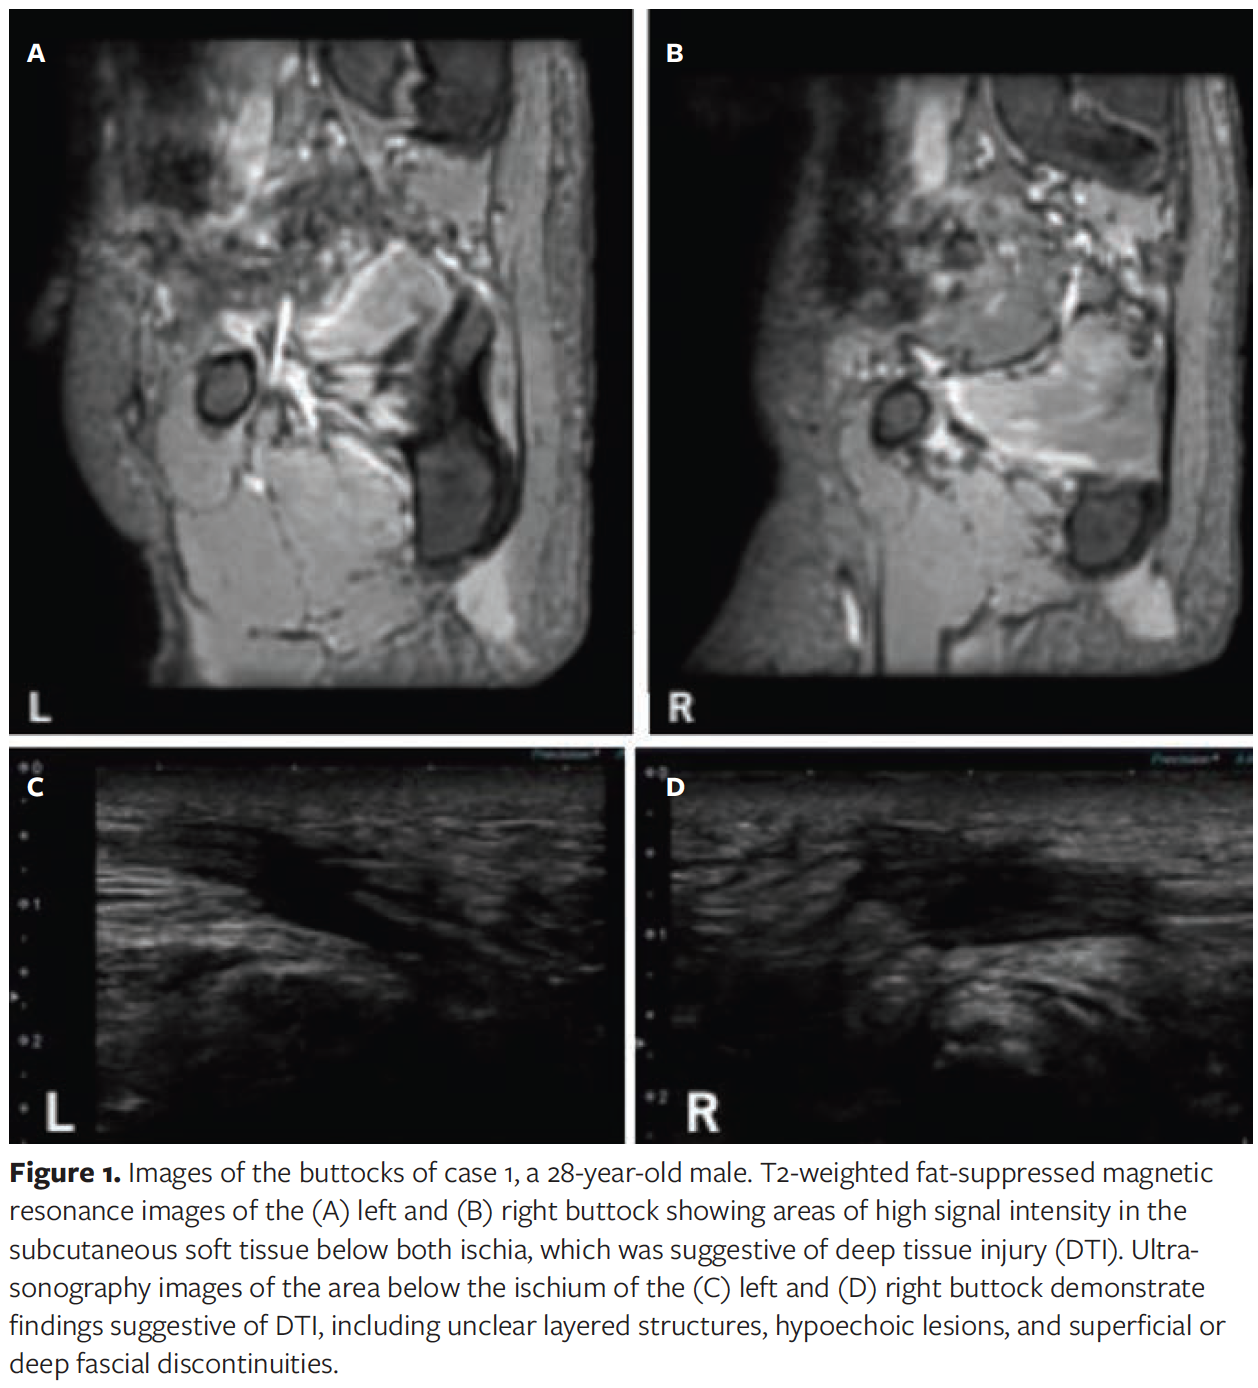

Case 1 is a 28-year-old male with incomplete paraplegia (American Spinal Injury Association Impairment Scale type B injury) at the C5 level resulting from a fall 3 years previously. He had undergone debridement and reconstructive surgery with a V-Y advancement flap at a previous hospital for osteomyelitis and deep pressure ulcer in the sacral region. He was transferred to Kibikogen Rehabilitation Center for Employment Injuries for postoperative rehabilitation. On physical examination at admission, no skin abnormalities were observed on the patient’s buttocks. However, MRI performed for postoperative follow-up of sacral osteomyelitis after admission showed areas of high signal intensity in the subcutaneous soft tissue below both ischia on T2-weighted fat-suppressed images, which were suspicious for DTI (Figure 1A, 1B). Ultrasonography confirmed findings suggestive of DTI, including an unclear layered structure, hypoechoic lesions, and superficial and deep fascial discontinuities (Figure 1C, 1D).

The characteristic ultrasonographic findings of DTI consist of an unclear layered structure, a hypoechoic lesion, discontinuous superficial or deep fascia, and a heterogeneous hypoechoic area.10 In particular, the presence of discontinuous deep fascia or heterogeneous hypoechoic areas are particularly concerning for DTI.10 In the current case report, although there was no abnormality on the skin surface in either case 1 or case 2, both patients had ultrasonographic characteristics of DTI as well as discontinuous fascia, and the authors of the current report were concerned that DTI could worsen in the future. In contrast, findings suggestive of DTI were observed on T2-weighted fat-suppressed MRIs, which clearly showed regions of high signal intensity in the subcutaneous soft tissues below the bone. In case 1, MRI findings showed abnormal shadows from both ischial tuberosities to the subcutaneous tissue, confirming the bottom-up theory of the progression of DTI development from the deep layers to the superficial skin as discussed in Ankrom et al.25 In case 2, MRI showed extensive abnormal shadows in the subcutaneous soft tissue of the left buttock. This finding is similar to that of a previously reported case of DTI in the thigh that was confirmed by MRI.13